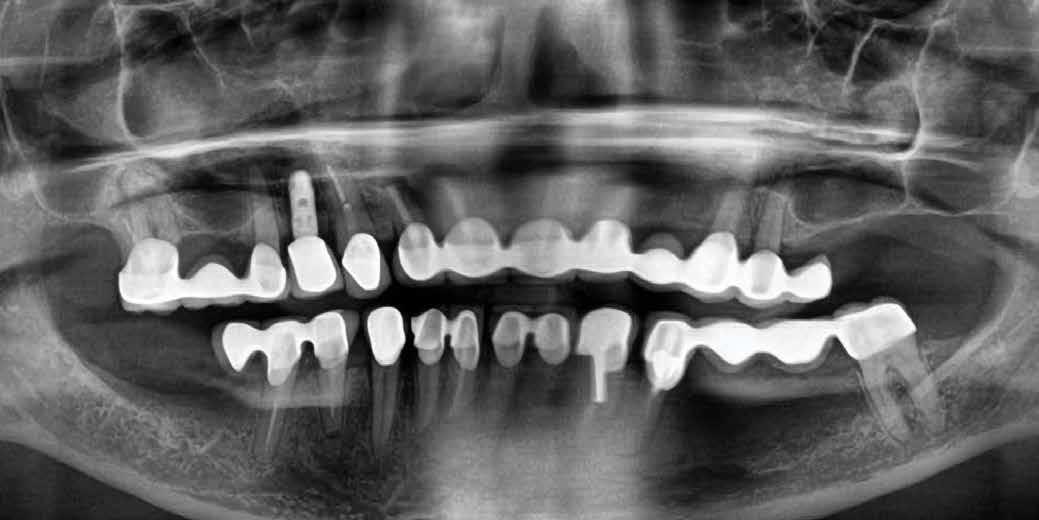

Kiindulási helyzet

A páciens egy 56 éves nőbeteg, nem dohányzik, általános egészségi állapota jó (ASA I), gyógyszert nem szed, ismert allergiája nincs. Fő panasza, amellyel klinikánkat felkereste, hogy elégedetlen mosolyával. Elmondása alapján az utóbbi években krónikus gyulladás alakult ki frontfogai körül, amely érezhető mobilitáshoz vezetett. Ez a probléma jelentősen befolyásolta a magabiztos beszédben és étkezésben. A páciens hosszú távú megoldást keresett, de aggódott a kezelések alatt fellépő esetleges fájdalom miatt. Az extraorális vizsgálat során megállapítottuk, hogy a mosolyvonal közepesen magas és a frontfogak torlódottak (1–2. ábrák). A szájüregi vizsgálat során a 1.2, 2.1 és 2.2 fogak körül előrehaladott parodontális tapadásveszteséget és mobilitást találtunk (3. ábra). A CBCT (cone beam CT) felvételen látszott, hogy a 2.1 fog bukkális csontfala hiányzik (4. ábra).

Az SAC-osztályozás alapján az eset sebészileg komplex, protetikailag egyszerű besorolást kapott (5. ábra).

1. ábra: Az extraorális vizsgálat közepesen magas mosolyvonalat mutatott.

2. ábra: A torlódott felső frontfogak.

3. ábra: Az intraorális vizsgálat során a bal felső nagymetszőnél és mindkét oldali kismetszőnél parodontális tapadásvesztést és mobilitást találtunk.

4. ábra: A CBCT-felvételen látható a buccalis csontfal hiánya.

A 2.1-es implantátumról öt hónappal a beültetést követően kontrollröntgen készült, amelyen ellenőriztük a gyógyulást és az implantátum pozícióját a csontban (11. ábra).

6. ábra: A bal felső nagymetszőt és a két kismetszőt eltávolítottuk, majd a jobb felső nagymetszőt és a szemfogakat előkészítettük. – 7. ábra: Akrilát ideiglenes híd. – 8. ábra: A gyógyulást követően horizontális és vertikális csonthiány látszik a bal felső nagymetsző területén. – 9. ábra: Hat hónappal a fogeltávolítást követően: a gyógyulása zavartalan volt. 10. ábra: A 1.2 helyére egy 3,3 mm átmérőjű, a 2.1 helyére pedig egy 4,1 mm átmérőjű Straumann® Roxolid® SLActive® BLT implantátum került. – 11. ábra: Öt hónappal a beültetést követően kontrollröntgen készült a 2.1 implantátumról, amelyen ellenőriztük az implantátum megfelelő pozícióját és integritását.

Kezelési eredmények

A végleges lenyomatvétellel egy időben kontrollröntgeneket készítettünk az implantátumokról, hogy pontosan felmérhessük azok pozícióját és a környező szövetekhez való viszonyát (15. ábra). Hat évvel a kezelés befejezését követően a hosszú távú stabilitás és a szövetek egészségének ellenőrzésére utánkövetéses röntgenek készültek (16. ábra). A hat- (17–18. ábrák) és a kilencéves (19. ábra) utánkövetés során az átfogó klinikai és röntgenvizsgálatok kedvező eredményeket mutattak az osszeointegráció, az implantátumok körüli csontsűrűség és az esztétika terén is. Ezen eredmények együttesen a kezelés hosszú távú sikerét jelezték. A kezelés a kemény- és a lágyszövetek esetében is rendkívül egészséges állapotot eredményezett. A páciens nagyon hálás volt, hogy a kezelés minden apró részletére gondosan ügyeltünk.

12. ábra: A hét hónapos kontroll alkalmával sikeres lágyszöveti gyógyulás látható. – 13. ábra: A végleges fogpótlás. – 14. ábra: A végleges koronák megjelenése esztétikus. – 15. ábra: A végleges lenyomatvételkor készült kontrollröntgenek igazolják az implantátumok pontos pozícióját és a környező csont épségét. – 16. ábra: Az utánkövetéses röntgenvizsgálatok során értékeltük az implantátumok körüli szövetek hosszú távú stabilitását és épségét. – 17. ábra: A hatéves kontrollnál kedvező esztétikai eredmény látható. – 18. ábra: A hatéves kontrollnál kielégítő klinikai eredmény látható. – 19. ábra: A kilencéves kontroll alkalmával látható, hogy a kemény- és lágyszövetek egészsége megtartott.